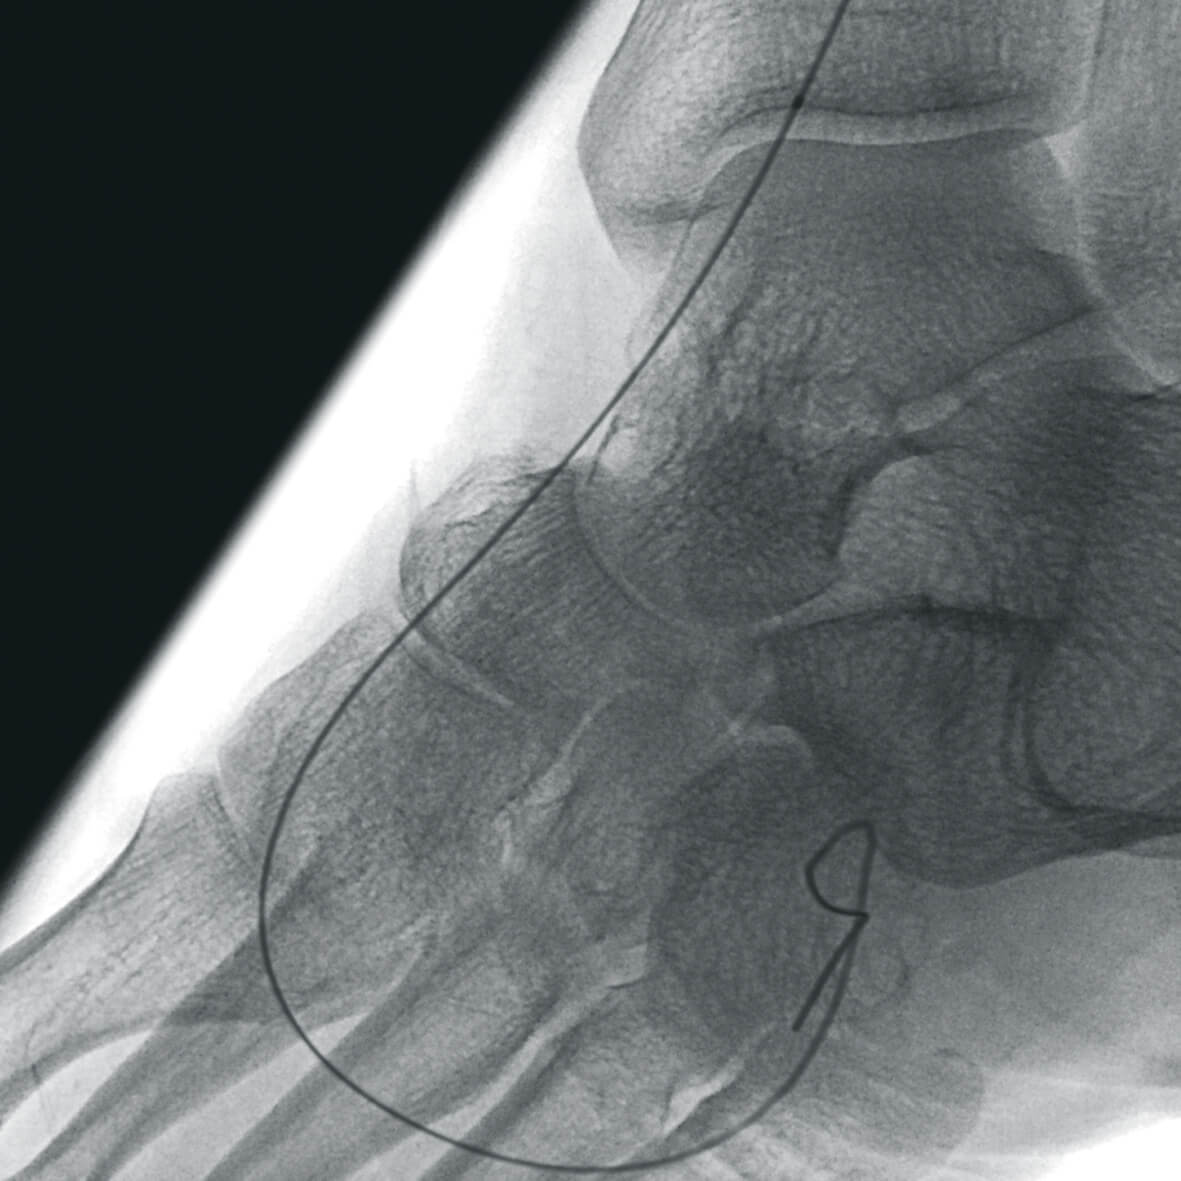

Полное отсутствие искажений снимков в сочетании с высоким динамическим диапазоном широко востребованы как при сложных операциях в нейрохирургии, сосудистой хирургии, инвазивной радиологии, так и в гибридных областях применения, а также в ортопедии, травматологии. В сосудистой хирургии особенно важны высокий динамический диапазон и пространственное разрешение, обеспечивающие детальную визуализацию даже мельчайших сосудов. Специализированное программное обеспечение SmartVascular позволяет проводить настройку системы для васкулярных операций и сосудистой хирургии.

Точная визуализация анатомических деталей, мягких тканей и костных структур обеспечивается за счет светочувствительной матрицы 3kх3k пикселей с высоким динамическим диапазоном.